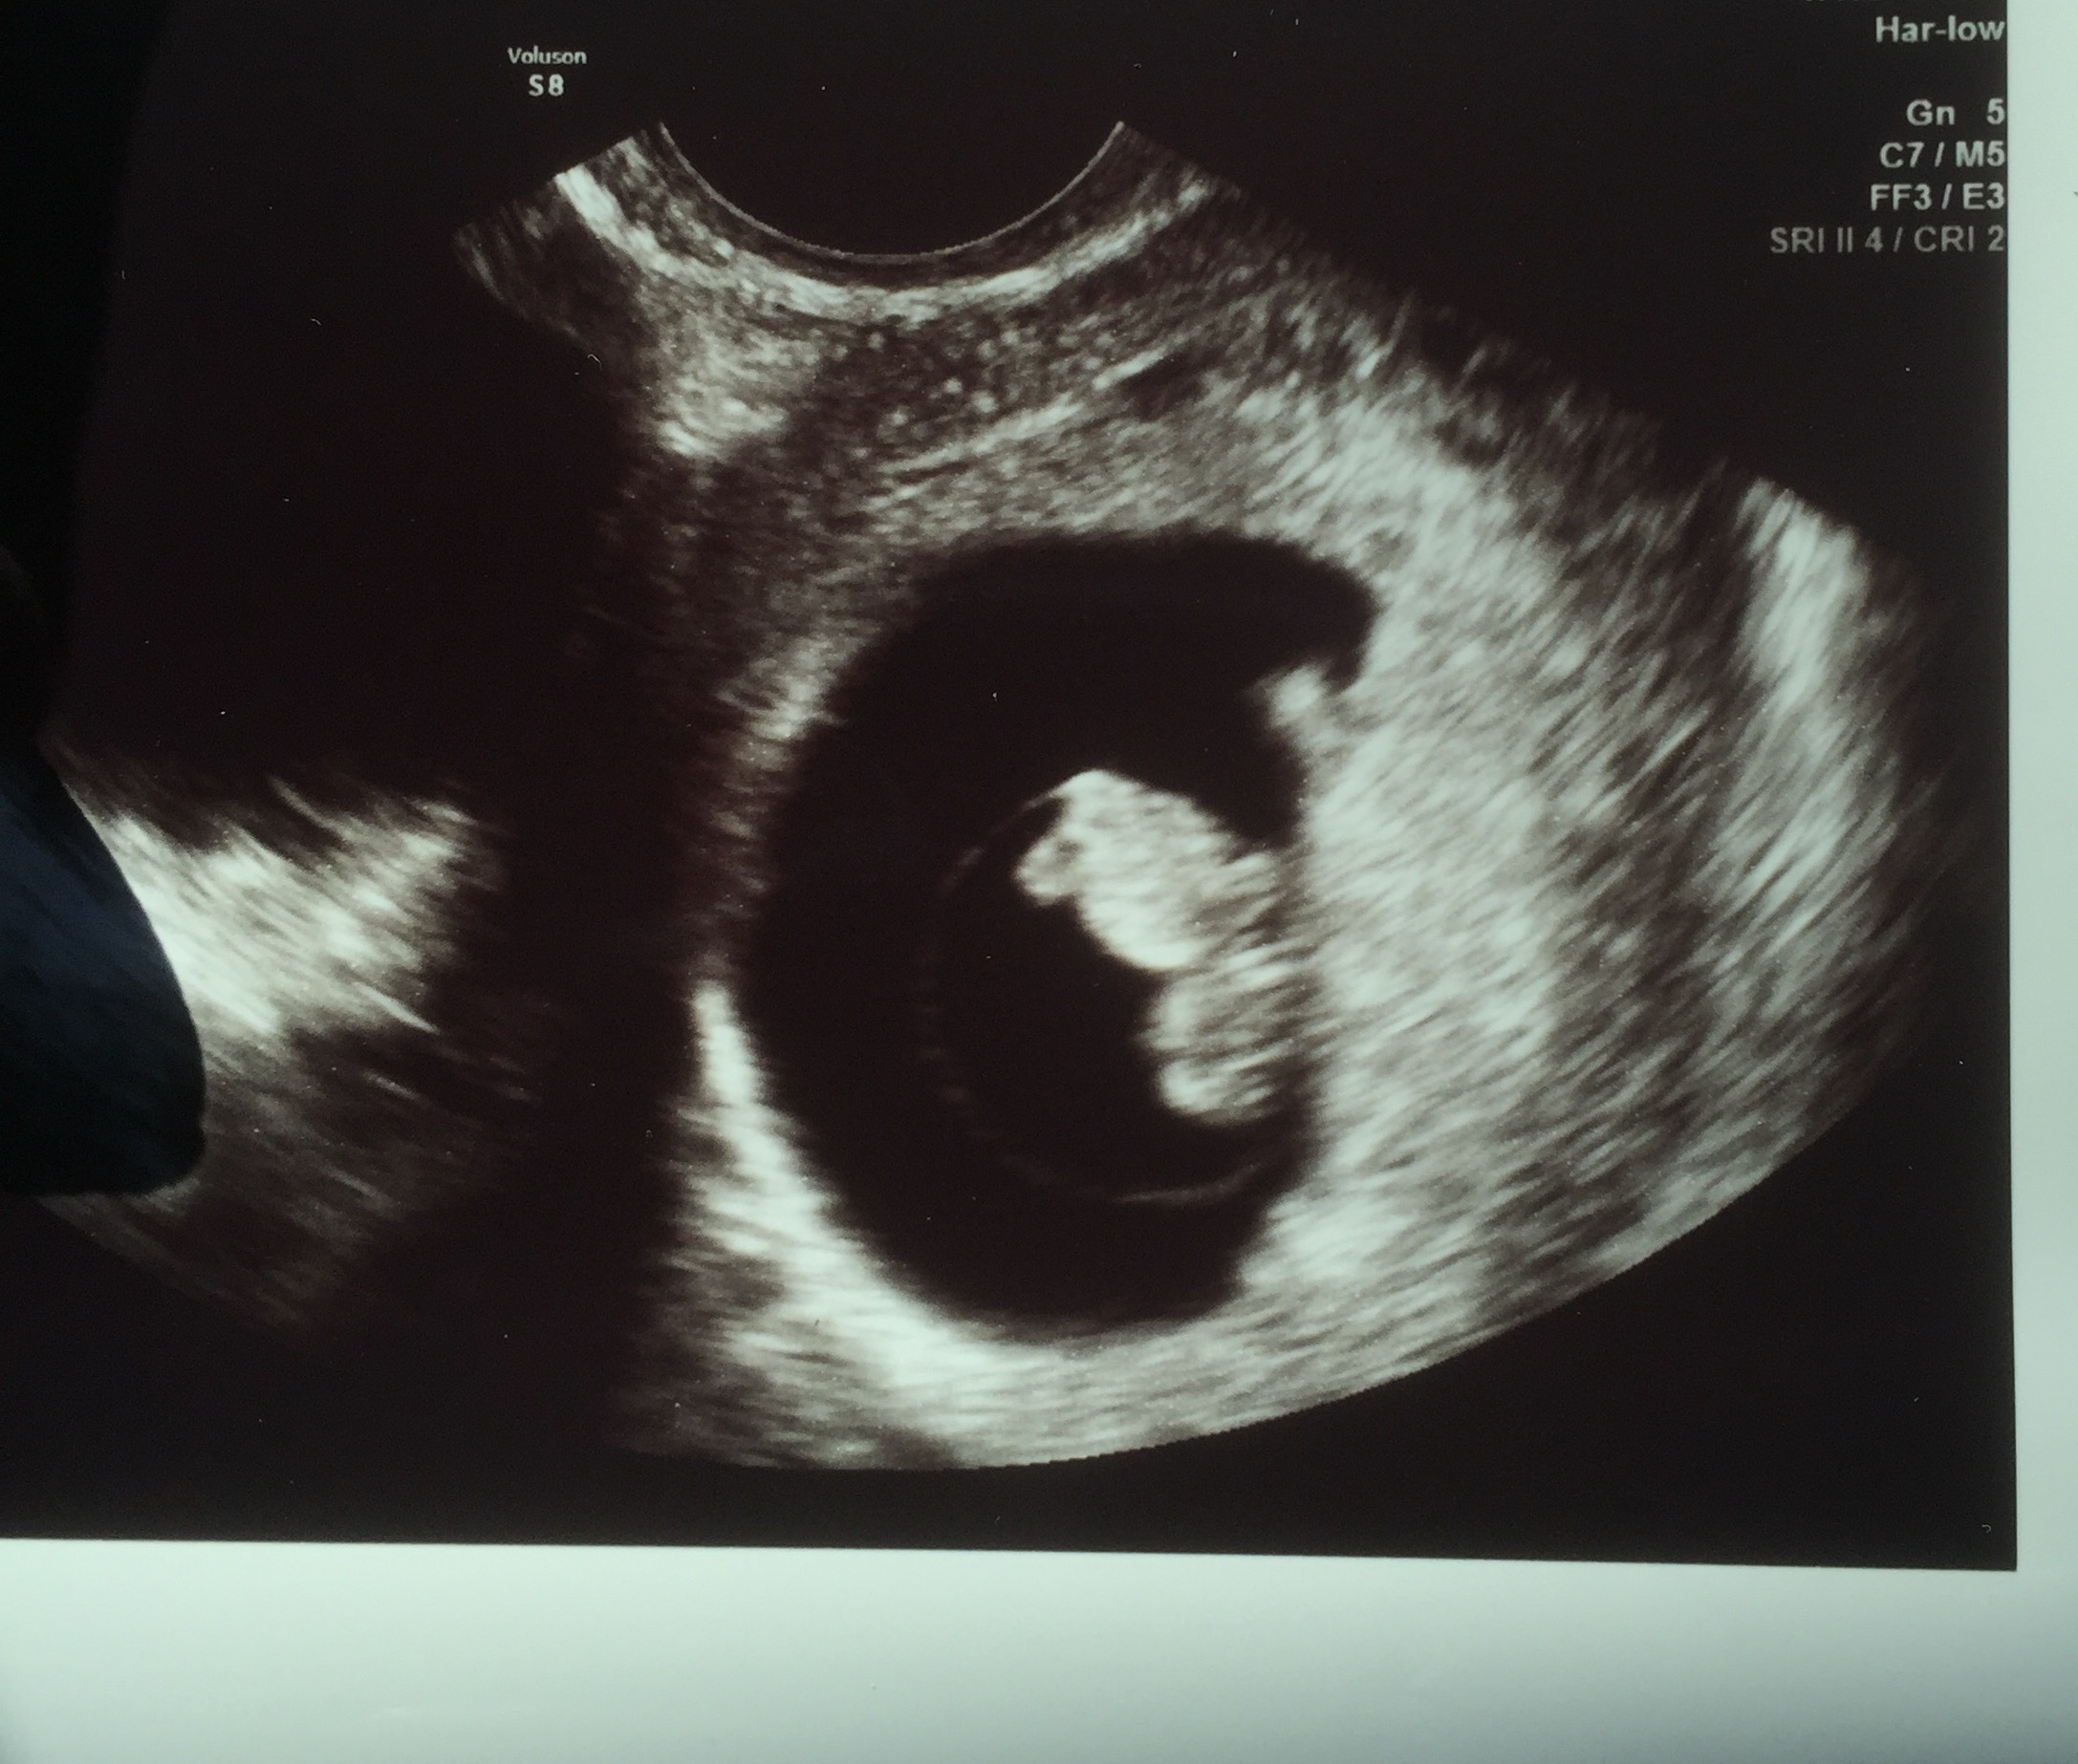

• Had another US yesterday! Measured 8w6d (right on track!), heart rate 174 and got to see our little gummy bear moving around. Next week is my last weekly ultrasound and then I will be every 2-4 weeks. So glad my OB takes us seriously and likes to keep my anxiety down a bit. Hoping at the next one he's able to do a clear abdominal ultrasound! The vaginal gets a bit old.